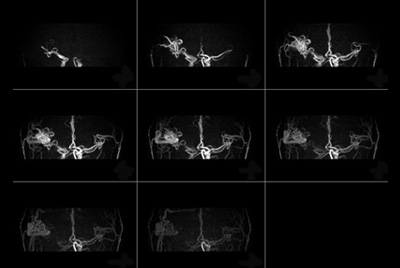

Dynamic contrast-enhanced MR Angiography